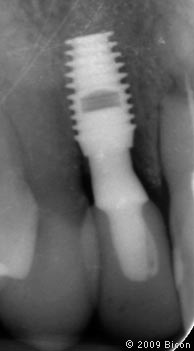

64. Рентгенограмма после установки

65. Рентгенограмма после установки